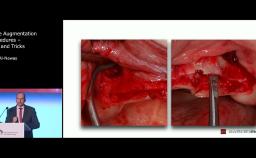

This lecture presents the different types of digitally assisted and/or guided implant placement technologies, including Static Computer Assisted Implant Surgery (S-CAIS), Dynamic-Computer Assisted Implant Surgery (D-CAIS) and Robotic-Assisted Implant Surgery (RAIS). Dr. Gallucci explains how digital assistance not only facilitates virtual planning but may also elevate the treatment outcomes, offering improved design precision, increased reproducibility of treatment rendered, and a safeguard against failure or complications. Moreover, Dr. Gallucci also tackles the essential decision-making process regarding the use of digital guidance, distinguishing between its optional and essential roles in both standard and complex implant cases.